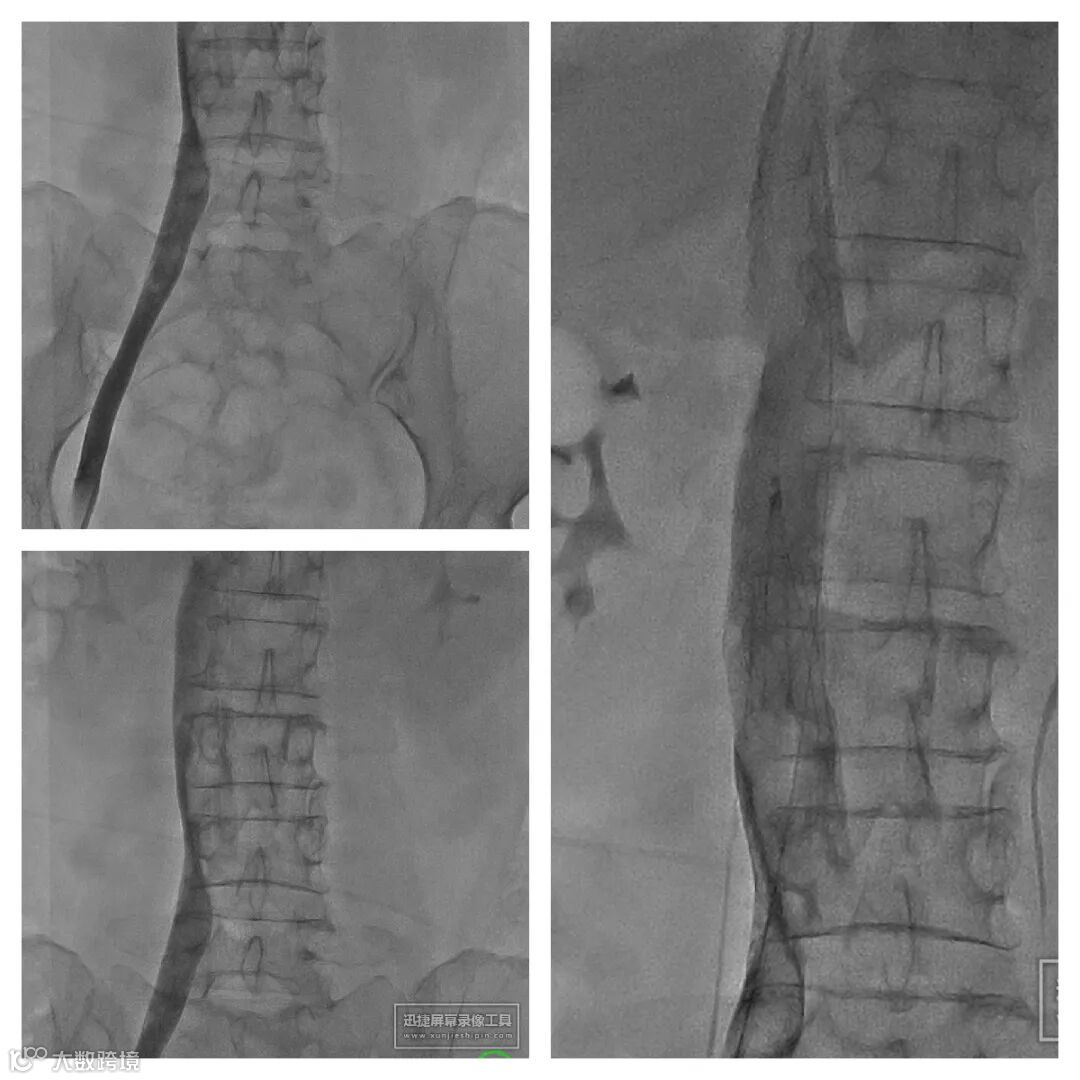

1. 超声引导下穿刺左腘静脉,置入6F鞘管,造影确认。

2. 右股静脉穿刺,造影示:下腔静脉血栓形成。小心通过后放置下腔静脉滤器。

3. 左腘静脉更换Tendfast®14F鞘管,造影示:左下肢全程静脉血栓形成。

4. 送入腾复Tendfast®外周静脉取栓支架,左股静脉拉栓1次,造影显示:左股静脉血流通畅。